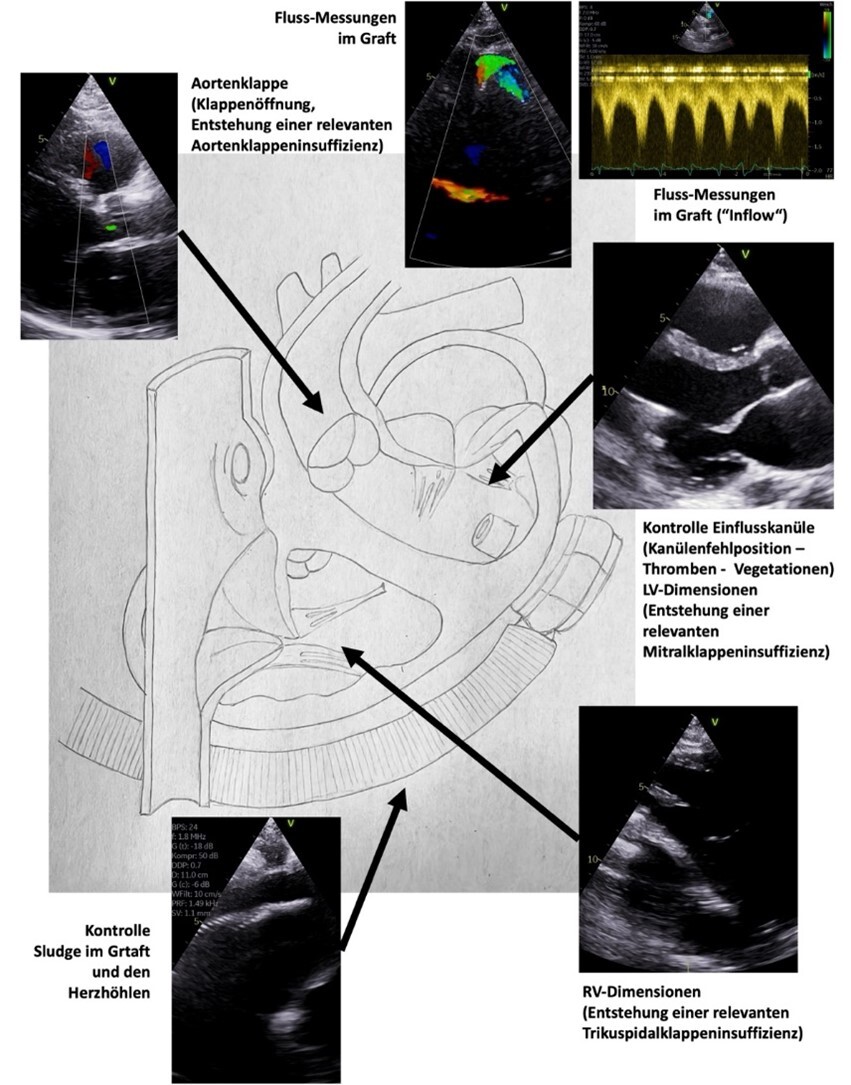

Zentrale Abbildungen aus dem Manual sind z. B. die Dokumentations-Protokolle mit der Kennzeichnung der Mindestanforderung durch „rote Punkte“ sowie die Anlotungen der echokardiographischen Kontrolle von LVAD-Systemen („left ventricular assist devices“):

Schemazeichnung zur echokardiographischen Kontrolle von LVAD-Systemen

Abb. 2: Schemazeichnung zur echokardiographischen Kontrolle von LVAD-Systemen („left ventricular assist devices“).